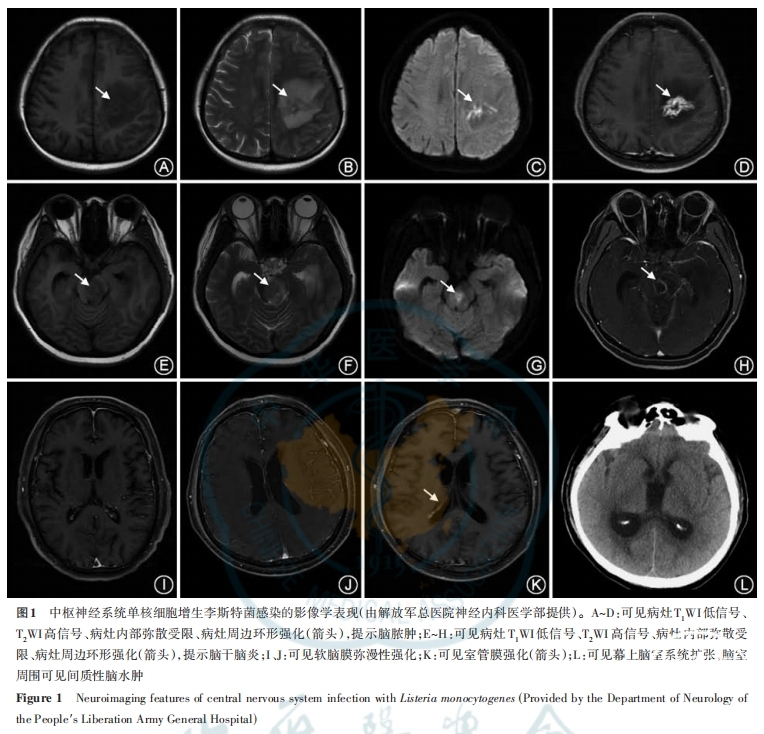

中枢神经系统单增李斯特菌感染可累及脑膜、脑实质、脑室及脑血管,并出现相应影像学表现(图1)[36-39]。MRI平扫及增强扫描对于病灶的显影优于CT平扫及增强扫描,应尽早完成。对于出现局灶性神经功能缺损症状(不包括脑神经麻痹)、新发痫性发作、意识障碍(格拉斯哥昏迷评分<10分)、严重的免疫抑制状态等高危患者,应在腰椎穿刺前行影像学检查评估脑疝风险[7]。

1.脑膜:CT增强扫描及MRI增强扫描可见脑膜强化。

2.脑实质:脑脓肿,多见于菱脑及灰白质交界区,CT平扫可见边界清楚或不清楚的低密度灶,CT增强扫描可见脓肿周边斑片状、不规则或规则的环形强化;MRI平扫可见病灶呈T1WI略低信号、T2WI中等或稍高信号,病灶内部弥散加权成像高信号,表观弥散系数降低,MRI增强扫描可见脓肿周边斑片状、不规则或规则的环形强化。脓肿周边伴水肿,CT平扫为低密度灶,MRI平扫呈T1WI低信号、T2WI高信号。此外,部分病灶可呈结节样强化。

3.脑室:(1)脑室炎:CT增强扫描及MRI增强扫描可见室管膜增厚和强化;(2)脑室脓肿:多位于沿重力方向的脑室下部,CT平扫可见较脑脊液稍高密度灶,MRI平扫可见较脑脊液T1WI稍高信号、T2WI稍低信号,弥散加权成像高信号,表观弥散系数降低;(3)脑积水:CT平扫及MRI平扫可见幕上、幕下脑室系统扩张,脑实质受压变薄。

4.脑血管:继发血管炎症,出现脑梗死及脑出血相关影像学表现。